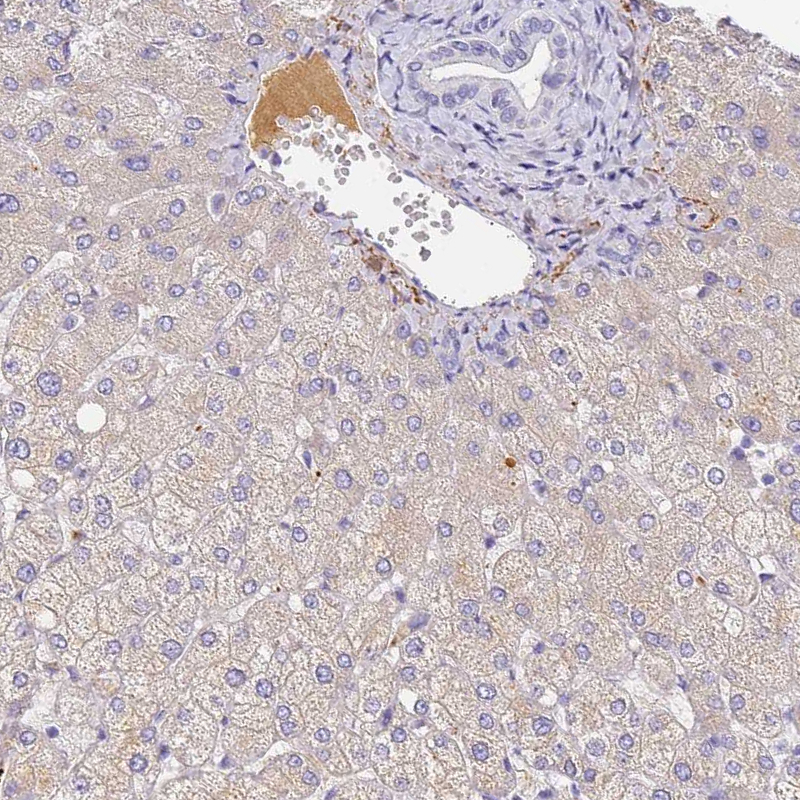

Immunohistochemical staining of human liver cancer, hepatocellular carcinoma shows strong cytoplasmic positivity in tumor cells.